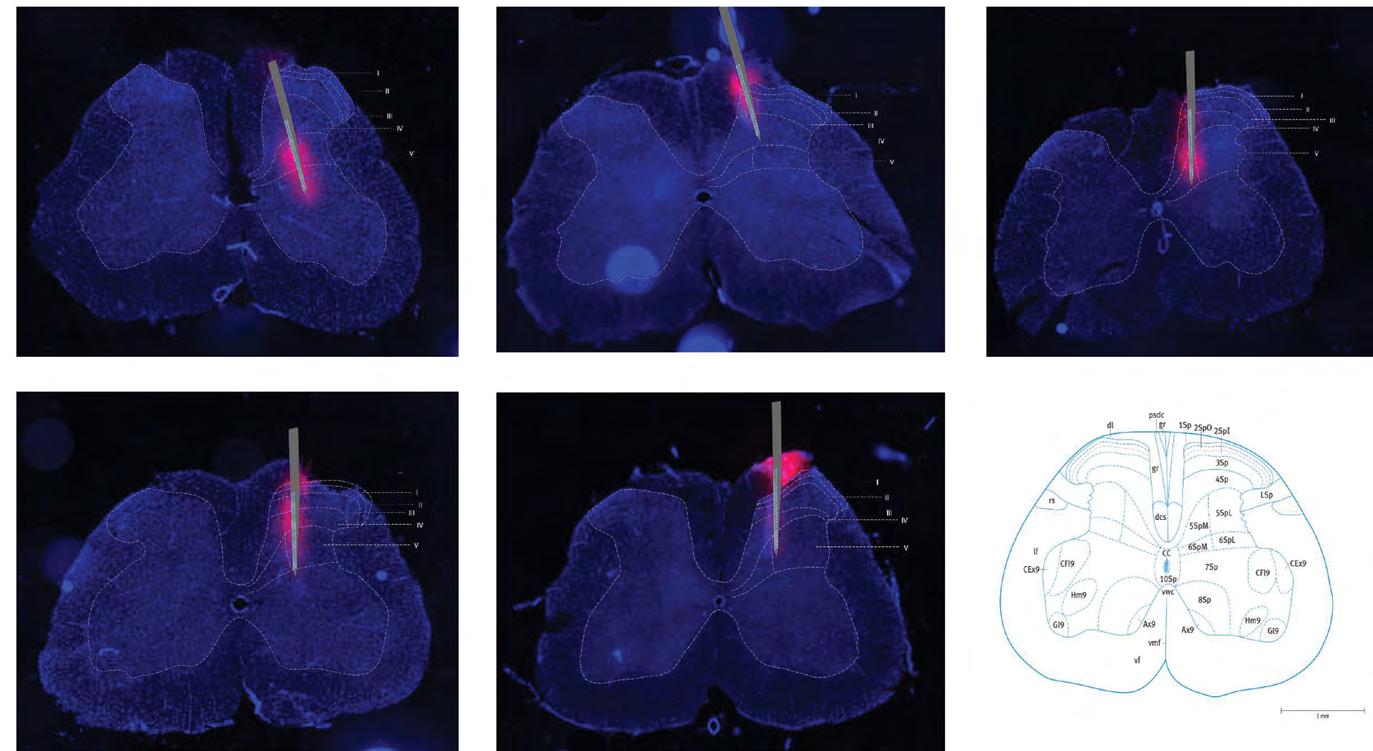

Figure 6 Final images produced using Inkscape vector graphics. 5 spinal cord sections from the lumbar region at a 50μm thickness under a fluorescent microscope with an animal ID showing the relative probe position as compared to the structure of an L5 rat spinal cross-section. Neuronal cell bodies in blue highlighted by the DAPI stain and the area of probe insertion in red highlighted by the DiI stain.

Table 2: Means and standard deviations of probe placement in the spinal dorsal horn. Major axis length: length of fluorescence produced by the macro instruction. Probe depth: depth of the probe from the top of the section. Medial-lateral: Horizontal deviation of the probe from the middle of the section. Orientation: Angle at which the probe was inserted taken counter-clockwise from the horizontal. Lamina: Shows the lamina number in which the probe tips reached.

Values for the probe positions in sections A-E were calculated using Inkscape and the means and standard deviations for the measurements are shown in Table 2. Individual measurements for the probe depth are represented in Graph 1 below. These results can be used to accurately confirm the position of the probes when used in conjunction with the electrophysiological data.

Across the 3 sets of data presented below, the peak responses were recorded on electrodes in rows 20 to 40 as shown on the SEP waveforms. When compared to the images created on Inkscape (Figure 6) and the probe depth measurements (Graph 1), this directly correlates to lamina IV-V in the lumbar spinal dorsal horn. However, the probe in section A has been inserted deeper which explains why the peak amplitude of the N1 potential is recorded towards the top of the probe. The peak amplitude in recorded in sections B and C is more central as the probe is shallower in the spinal cord. Therefore, the N1 potential is recorded on medial channels.

The fluorescent dye successfully stained the position of the probe and the cell bodies of neurons within the spinal dorsal horn across 5 rats. The anatomical features of the sections identified with DiI fluorescence closely match those of lamina V of the spinal cord, confirming the expectations of the electrophysiology. Figure 6 also shows a similarity regarding the shape and size of the sections. This holds true when compared to the cross-sectional image of the rat L5 spinal cord from the rat spinal cord atlas, especially with regards to the shape of the grey and white matter.